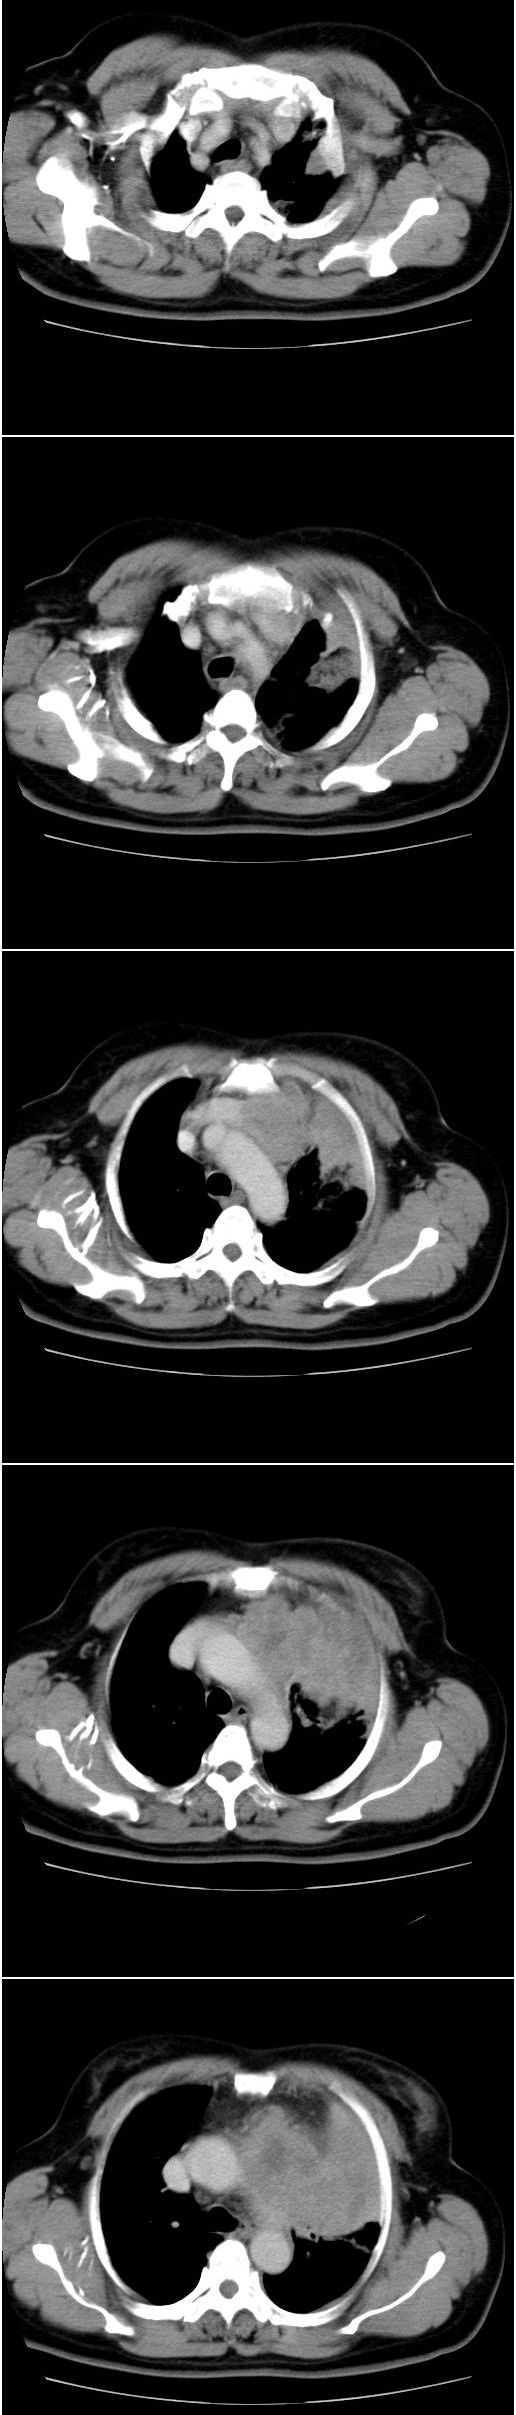

标题: CT13028:女,56岁。咳嗽、气促一月,咳血一周。CT值增加约30 [打印本页]

标题: CT13028:女,56岁。咳嗽、气促一月,咳血一周。CT值增加约30

左上肺肿块伴阻塞性改变,考虑肺癌可能大

感觉病灶主要来源于前上纵隔,向周围浸润,考虑为侵袭性胸腺瘤。

考虑左上肺癌(周围型)伴左肺门及纵隔转移(主肺动脉窗旁病灶可能为肿大并坏死的淋巴结),不除外纵隔型肺癌

软组织肿块,应该有肺不张(因为左膈及脾脏\\胃抬高明显):考虑中央ca

支持纵隔旁型肺癌伴主动脉弓\\主肺动脉及左侧头壁动脉受侵.

考虑左肺中心性肺癌并纵隔淋巴结转移,累及左肺动脉及左侧头臂静脉.但不除外纵隔恶性肿瘤累及肺组织.

考虑左肺中心性肺癌并纵隔淋巴结转移,纵隔恶性肿瘤累及肺组织的可能性小,因为后者一般不会导致横膈上抬。

考虑左侧中央型肺癌伴左肺上叶肺不张及前纵隔淋巴转移。

1)考虑为:左肺上叶中心型肺癌伴左肺上叶阻塞性肺炎、节段性肺不张,左肺门及纵隔淋巴结转移。2)左侧少量胸腔积液。